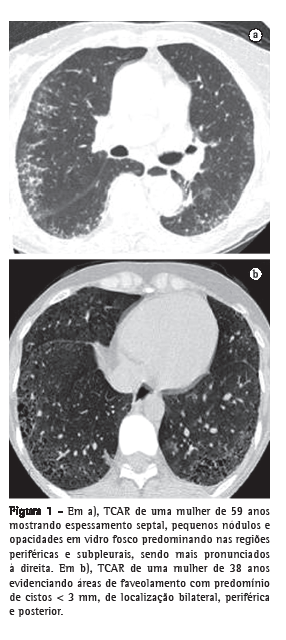

b) TCAR realizada com um aparelho GE (modelo HiSpeed LX/i; General Electric Medical Systems, Milwaukee, WI, EUA), com cortes com espessura de 1,0 mm, intervalo de tempo de 1,5 s, incremento de 10 mm, reconstrução de imagens com matriz de 512 × 512 pontos com algoritmo de alta resolução, largura de janela de 1.000 UH e nível médio de janela de −700 UH. A interpretação dos achados tomográficos foi feita de maneira independente por dois radiologistas com experiência em doença intersticial pulmonar. A TCAR foi analisada procurando-se os seguintes achados: pequenos nódulos, opacidade em vidro fosco, espessamento septal, faveolamento e bronquiectasia de tração. Para fins comparativos, os pacientes foram divididos em dois grupos, de acordo com a presença ou não de faveolamento (Figura 1).

A TCAR é atualmente considerada o exame radiológico de ponta na detecção do acometimento pulmonar. Áreas de faveolamento podem ser observadas na TC, especialmente nos casos de PIU e, em geral, também ocorrem áreas de opacidade em vidro fosco de permeio.(6,9,20) São vistas principalmente nas bases, predominando nas regiões periféricas e posteriores dos pulmões e, com frequência, associam-se a bronquiectasias de tração. Através da TCAR, observamos o aspecto de favo de mel em 48,6% dos casos, o que está de acordo com a frequência apresentada em outra casuística brasileira, que foi de 56%.(7)